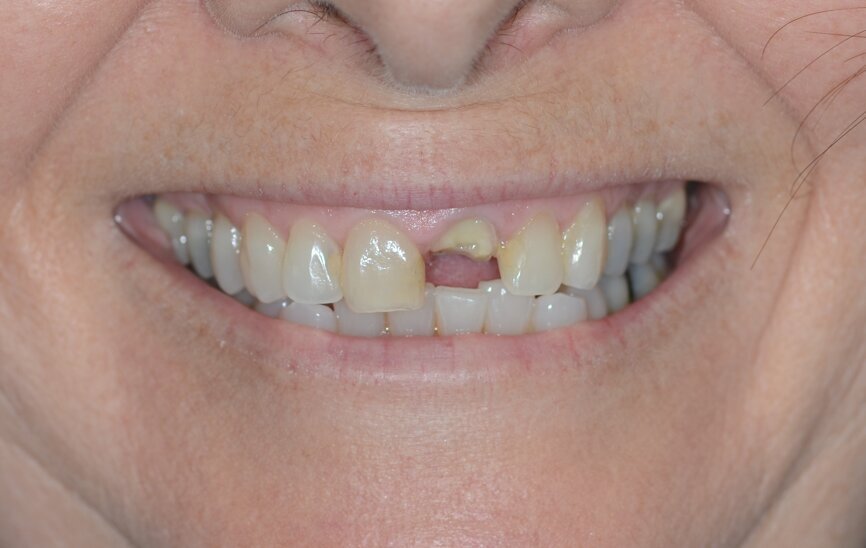

A 53-year-old female patient presented to the office with a fractured left central incisor which had been repeatedly bonded to a ceramic crown (Figs. 1 & 2). Anamneses and examination established good systemic and oral health, a well-balanced occlusion and no smoking habits. Cone beam computed tomography (CBCT) and a periapical radiograph showed external root resorption with very limited insertion into the alveolar bone, insufficient for adequate conventional intra-radicular post placement (Figs. 3 & 4). Considering that the fractured tooth was in the aesthetic zone, the patient requested restoration in the safest and fastest way possible.

Fig. 1: Initial situation, extra-oral view.

Fig. 2: Initial situation, intra-oral view.